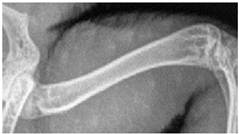

For this study, exclusively skeletal structures were examined. Four different structures (femur, ribs, vertebra, and phalanx) were chosen based on different bone architecture or features such as the differentiation of bone to soft tissue and surroundings (Table 3). The femur was essentially chosen to evaluate the differentiation between corticalis and spongiosa, joint structures were evaluated based on the left front phalanx, and the last left rib was used to further evaluate the details and structure of the corticalis. For each anatomical structure, four different characteristics (Table 3) were evaluated using a four-scaled scoring system, ranging from 1 (optimal evaluation) to 4 (insufficient evaluation). Scoring systems were used according to the modification of Körner, M. et al. [25] (Table 4).

In the present study, different skeletal structures of varying thickness and structure were used to have a broader spectrum of differences such as the transition from spongiosa to corticalis (femur, criterion 1) or demarcation to the joint (phalanx, criterion 2). Visceral structures were not assessed due to the use of dead bodies and the general challenge of assessing visceral structures with digital radiography in reptiles [2,9]. Visual grading characterizing (VGC) analysis was used and is recommended to evaluate the performance of different radiography systems. By using visual grading, anatomical criteria can be evaluated objectively with a link to clinical interpretation. Still, bias can occur, in this case primarily regarding the reviewers rating the systems. The reviewers were chosen regarding their experience with radiography in reptile species with a minimum of two years of experience in regularly evaluating radiographs in a specialized clinic. A training session was conducted beforehand to reduce divergence in scoring and achieve standardization. However, scores did differ significantly from each other (except for reviewer 1 compared to 4), showing the importance of subjectiveness and individual experience by different human beings even when using a scoring system. The disadvantages and advantages of VGC analysis have already been described in other studies such as Tebrün, W. et al. [13], Båth, M. et al. [29], and Månsson, L. G. [30]. Despite a lack of agreement in scores, the tendency with which the reviewers did score the criteria was the same. Therefore, assessments were significantly correlated for all criteria and all reviewers. These correlations prove the validity of the method, as the interpretation of the study results exclusively relies on the comparison of the scores between the system and dosages.

4.3. Effect of Dose Reduction

Data showed that in every system, a dose reduction led to significantly worse scores for most of the criteria, especially in the “double” reduction from 100% to 25%. Regarding the criteria, the vertebra seems to be the most sensitive structure with significantly worse scores after every reduction with each system used. In contrast, the ribs showed the least influence of the dose reduction, only receiving decreased scores after a reduction of 25%. The effect of dose reduction for the criterion femur varied. In the ribs and femur, the reviewers had to evaluate the differentiation between the bone, whilst in the criteria for vertebra and phalanx, the demarcation to the surrounding tissue and joint space was addressed. The vertebra and phalanx are much more delicate structures than the femur and rib, indicating a possible greater impact of dose reduction on smaller structures. In particular, the joint space with a fine surface and superimpositions of other structures could therefore be more affected than more solid structures such as the femur. The ribs are much more delicate than the femur, impeding the evaluation of this criterion and possibly leading to a greater impact in dose reduction, again indicating a greater influence on smaller structures. In contrast, the femur showed the best scores, indicating that the thicker and bigger the structure, the higher the chance of being able to evaluate variances.